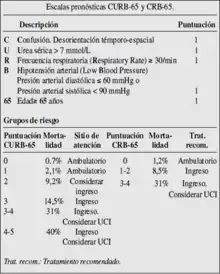

Clasificación pronóstica

Existen dos clasificaciones pronósticas de la neumonía o pulmonía:

El modelo CURB65 (estado de Conciencia, valor de la Urea, frecuencia Respiratoria, presión Arterial —Blood—, mayor de 65 años) o CRB65 valora 5 aspectos y la edad mayor a 65 (de ahí el acrónimo CURB65), el cual permite estratificar a los pacientes en 5 categorías de gravedad, con probabilidades de muerte entre 0,7 % si tiene 0 puntos, al 40 % si tiene 4 puntos o más. También es útil para valorar la necesidad de ingreso.